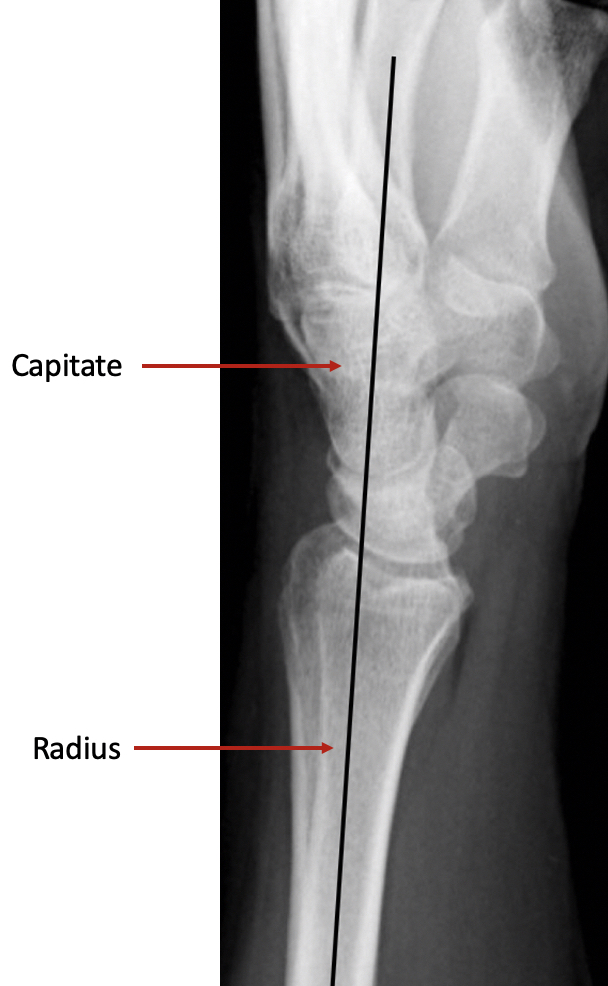

The surgery involves making an incision over the area of the malunion, and using a fine saw, the bone is divided. The bones are then repositioned in a more normal alignment and usually a small plate is used to fix the bone in its new position. On a normal side view xray (lateral view), if you draw a line up the middle of the radius bone, then this line should continue through the middle of the capitate bone. In a malunion, the continuing line does not pass through the middle of the capitate. The aim of surgery is primarily to restore this line.